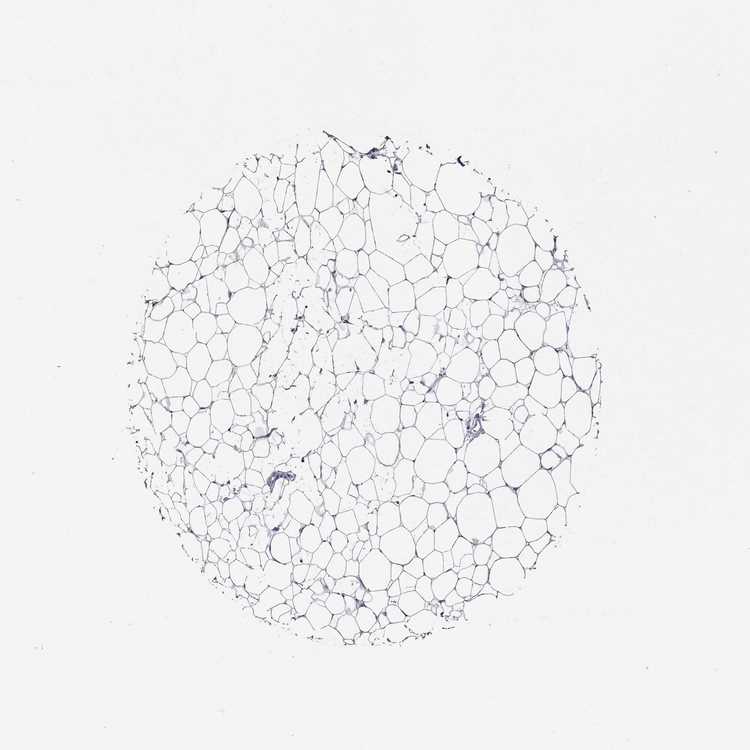

Each image is clickable and will lead to virtual microscopy that enables deeper exploration of all samples and also displays staining intensity scores, fraction scores and subcellular localization as well as patient and tissue information for each sample.

Antibody HPA052006

Adipocytes Not detected

Glandular cells Not detected

Myoepithelial cells Not detected